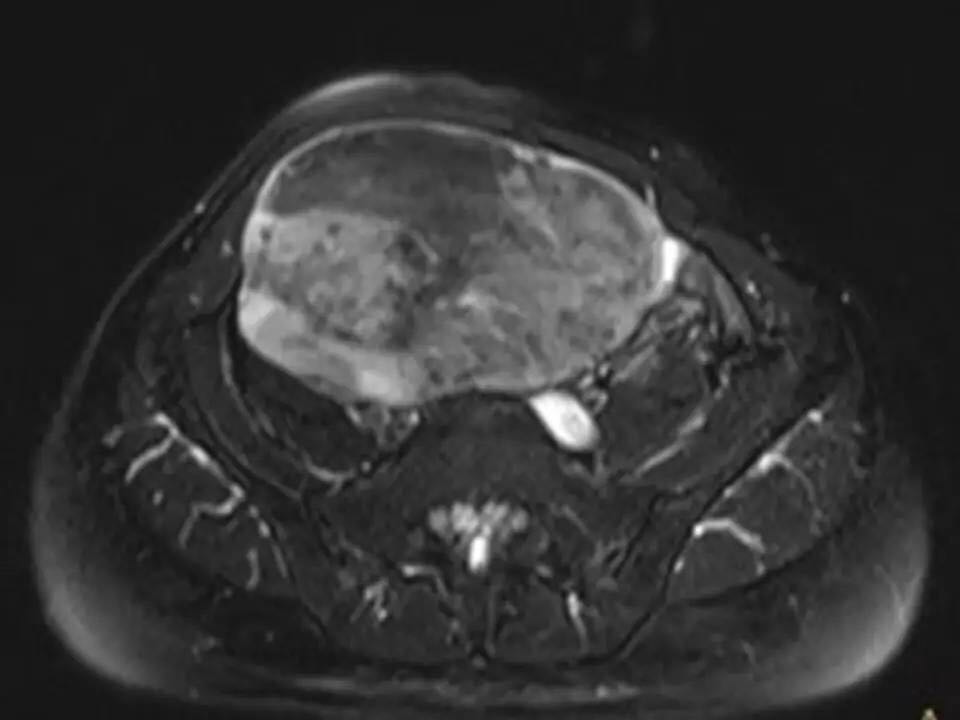

MRI表现,腹盆腔见不均质肿块,与肌肉相比为等低密度,强化不明显。T1WI信号均匀,T2WI高低混杂信号,增强后渐进性强化,病变各序列可见斑片状低信号区。 诊断,腹腔侵袭性纤维瘤病。

AF的影像学表现具有一定特征性。影像上表现为边界欠清的软组织肿块,钙化、出血少见,即便在较大的肿瘤中也看不到中央性坏死。病灶CT密度欠均匀,与邻近骨骼肌相近,强化不明显。T1WI信号基本均匀,明显或中度强化,典型强化方式呈渐进性。所有序列中都可以看到一定的低信号区,在病理上相对应的为病变内胶原纤维丰富的区域,此区域强化较轻。 侵袭性纤维瘤病虽然少见,但是平常工作中需要考虑到侵袭性纤维瘤病的诊断,尤其是中年女性腹腔的肿块。MRI为最佳的检查方法,可以显示一定的影像学特征。